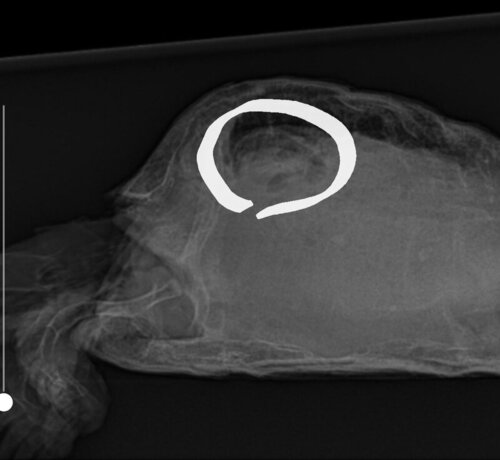

Вчера сделали рентген, на котором видно новообразование (7 месяцев назад его небыло). Ветеринар сказал заказать препарат саркомин, но его сейчас нет в продаже, может есть какие то аналоги, или кто то знает, где его можно купить? Чуть позже сегодня будет результат биохимии крови

по рентгену я не вижу новообразований.

У неё очень сжаты лёгкие, с большой вероятностью желудком и кишечником

Вот это сказали новообразование, вторая фотка рентген 7 месяцев назад

это больше похоже на каловый завал, но я подожду что наш герпетолог ответит

@Кристина14254 наш врач ответила, что по рентгену невозможно определить что именно там находится

По рентгену это может быть и киста на печени, и желудок набитый едой, и абсцесс… очень много вариантов

в таких случаях делают кт или мрт для уточнения диагноза.